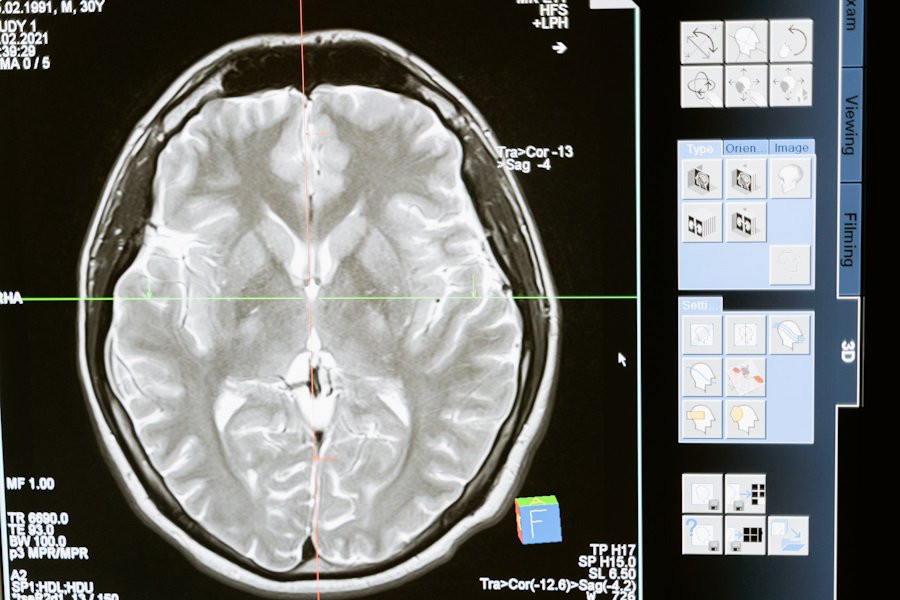

Согласно сообщению об исследовании, опубликованному на портале Science Robotics, ученые из Harvard Medical School (Boston, США) успешно разработали двуручного эндоскопического хирургического робота, который может значительно снизить инвазивность операций на головном мозге.

Используя этого робота, управляемого джойстиком, исследователи демонстрировали эффективность в выполнении задач, аналогичных этапам резекции опухоли головного мозга.

Согласно опубликованному исследованию этот новый хирургический робот обеспечивает значительно больший рабочий объем на кончике троакара и позволяет выполнение бимануальных задач без повреждения ткани головного мозга. Кроме того, было отмечено, что многие задачи можно выполнять с его помощью быстрее, чем с использованием существующих ручных эндоскопических инструментов.